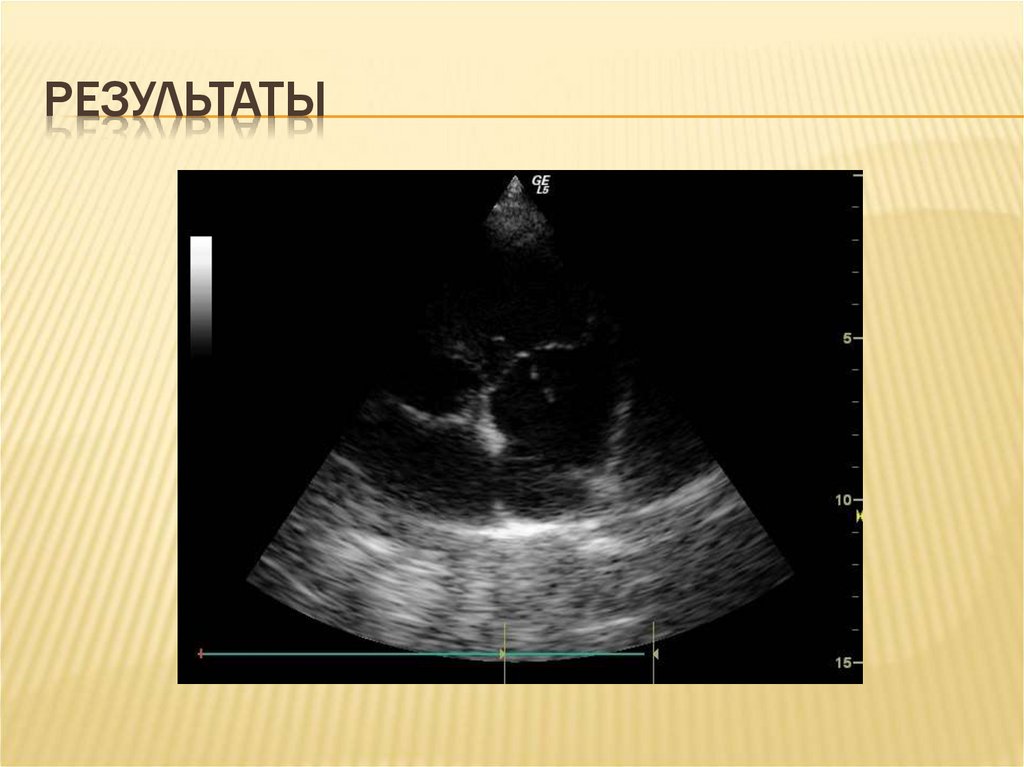

17. результаты

РЕЗУЛЬТАТЫ

18. результаты

22. Особенности эхокардиографического описания

ОСОБЕННОСТИ ЭХОКАРДИОГРАФИЧЕСКОГО

ОПИСАНИЯ

1.

2.

3.

4.

5.

Возраст вегетации (до двух недель, свыше

двух недель, с элементами организации)

Размер и площадь вегетации (до 2 см и

более 2 см в диаметре)

Вероятность отрыва (флотирующие,

соприкасающиеся вегетации)

Перегрузка правого желудочка

Поражение миокарда и перикарда